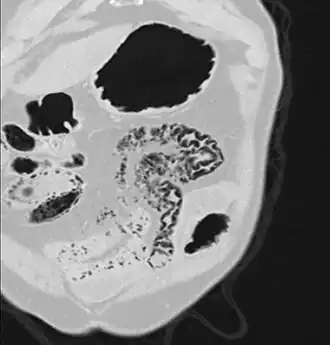

Pneumatosis intestinalis in the coronal computed tomography in lung window. It can be seen next to gas entrapment in the bowel wall and gas in the stomach wall and in numerous vessels, including the portal vein into the liver. -